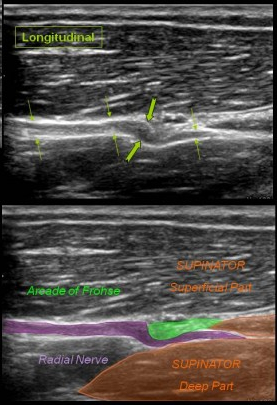

회외근 입구는

녹색으로 표시된 부위로

후로세 아케이드라고 하는데요.

딱딱한 섬유성 터널 구조로

되어있기 때문에

요골신경의 분지인

후골간신경의 마비가

잘 생기는 부위입니다.

여기서 신경이 압박되면

위 그림의 두꺼운 화살표로

표시된 것처럼

신경이 퉁퉁 붓게 됩니다.